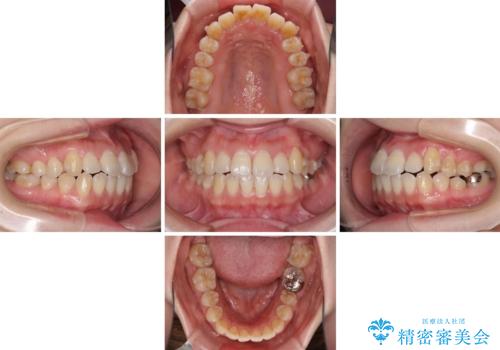

口元の突出感を改善 インビザラインによる非抜歯矯正

インビザラインでの歯列全体の後方移動は時間がかかりますが、しっかりと装着時間を守っていただいたので、スッキリとした口元に仕上げることができました。